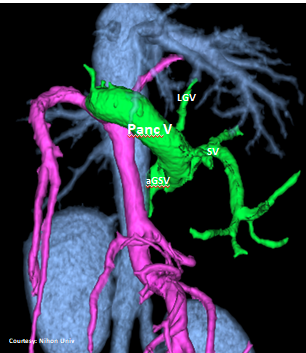

PRE-HEPATIC ENTRANCE

(Absent GSV)

“LGC +PancV -GSV” Left Gastro-Caval Shunt with Pancreatic Vein contribution and absent Gastro-splenic vein (GSV does not enter PV)

Courtesy: Nihon Univ